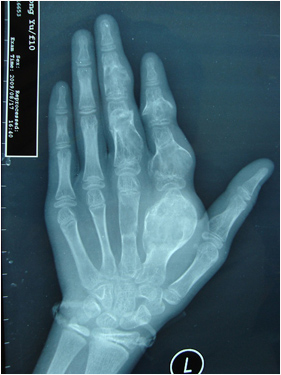

Ollier病-术后

蟹钳样复拇-术前